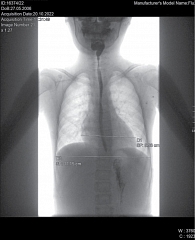

Рис. 1. Рентгенологическое исследование органов грудной клетки. Сердечно-грудной индекс – 0,58 (горизонтальный размер тени сердца – 9,98 см)

Рентген органов грудной клетки: отмечается повышенный горизонтальный размер тени сердца – 9,98 см. Сердечно-грудной индекс – 0,58 – повышен и характерен для начальной стадии дилатационной кардиомиопатии (рис. 1).